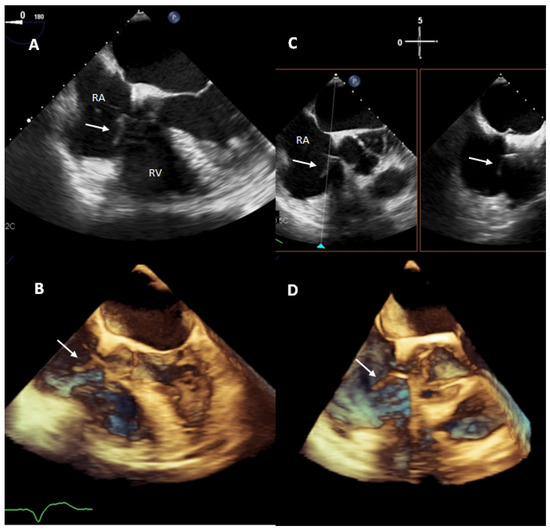

- Downey, B.C.; Juselius, W.E.; Pandian, N.G.; Estes, N.A.M.; Link, M.S. Incidence and Significance of Pacemaker and Implantable Cardioverter-Defibrillator Lead Masses Discovered during Transesophageal Echocardiography. PACE-Pacing Clin. Electrophysiol. 2011, 34, 679–683. [Google Scholar] [CrossRef] [PubMed]